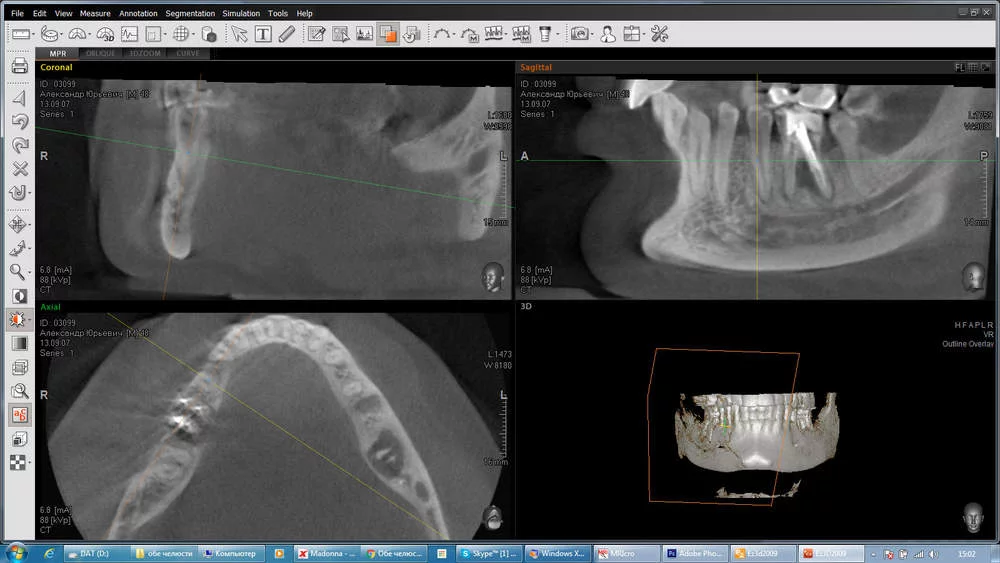

Вот так выглядит КТ другого типа

_02.webp

Это три проекции, которые просмотрщик показывает синхронизируя между собой.

Просмотрщики есть двуxмерные и треxмерные. Вот треxмерный inobitec. ru - позволяет строить трехмерное изображение, но тридцатидневное бесплатное использование. Не знала куда писать, поэтому в две темы.

))А что Вас так удивляет? Меня тоже оперировал этот доктор.Эти все замеры делаются в их КТ программе,там действительно спец.линейка в самой программе, а как иначе?На глаз? И это все доктор замеряет и показывает на консультации,а не во время операции.